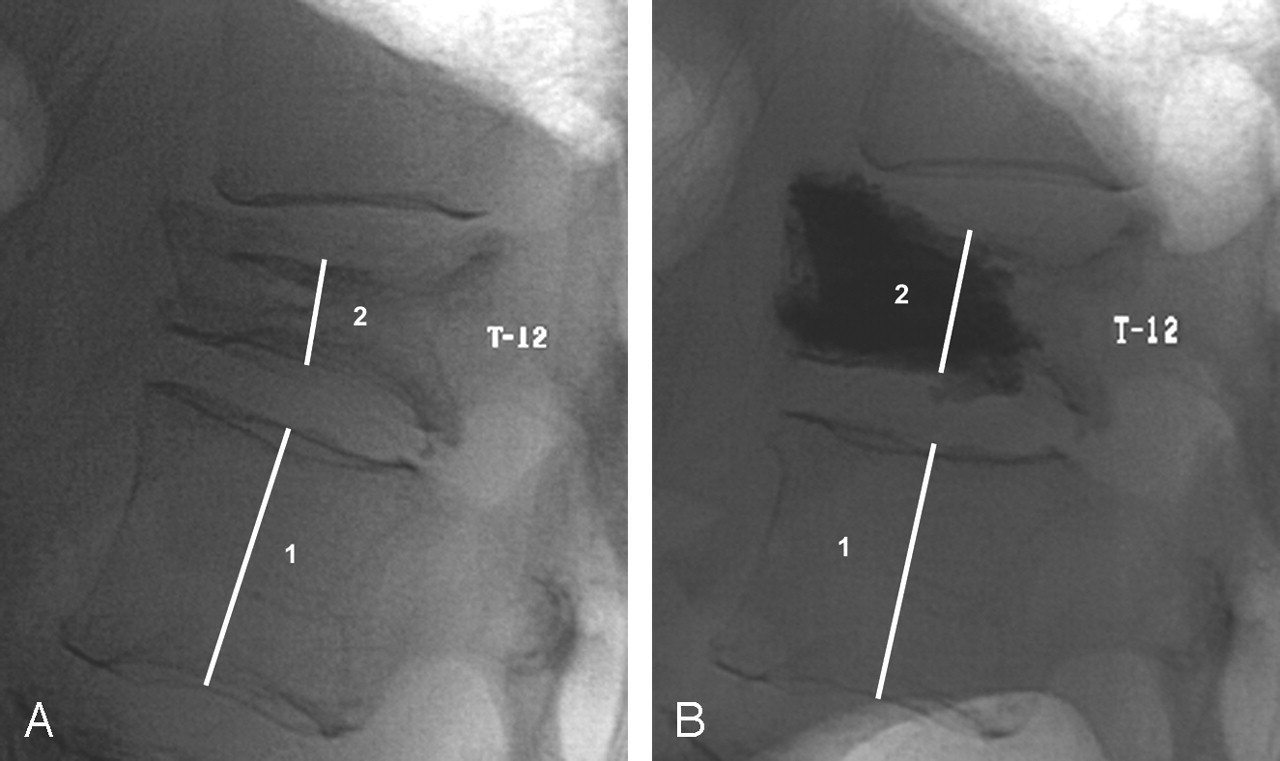

VERTEBROPLASTY FOR OSTEOPOROTIC FRACTURES

Osteoporosis is characterised by thin, fragile bones. Osteoporotic vertebral compression fractures are minimal trauma fractures of the vertebral (spine) bones (vertebrae). They can cause severe pain and disability. Vertebroplasty involves injecting medical-grade cement into a fractured vertebra through a needle inserted into the skin, under light sedation or general anaesthesia. The cement hardens in the bone space to form an internal cast.